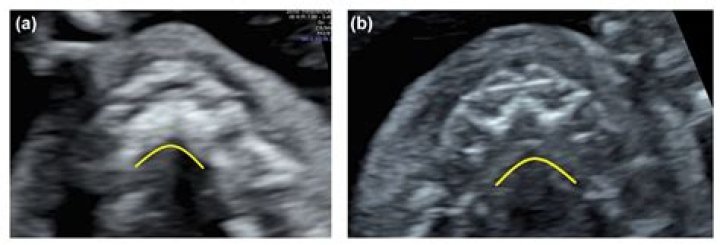

Prenatal Diagnosis of Cleft Palate

A regular ultrasound scan cannot reliably identify a cleft palate, either by itself or along with a cleft lip. If you have received a diagnosis of 'cleft lip and palate' from a regular ultrasound scan, it's very likely that what was actually found was a cleft lip and gum.

A cleft lip is usually picked up during the mid-pregnancy anomaly scan done when you're between 18 and 21 weeks pregnant. Not all cleft lips will be obvious on this scan and it's very difficult to detect a cleft palate on an ultrasound scan.

In most cases, a prenatal ultrasound can detect cleft lip alone or cleft lip and palate as early as 16 weeks into a pregnancy. The diagnosis is then confirmed at birth with a detailed visual assessment and physical examination.

3D ultrasound in high-risk women resulted in a detection rate of 100% for cleft lip, 86% to 90% for cleft lip with palate and 0% to 89% for cleft palate only.